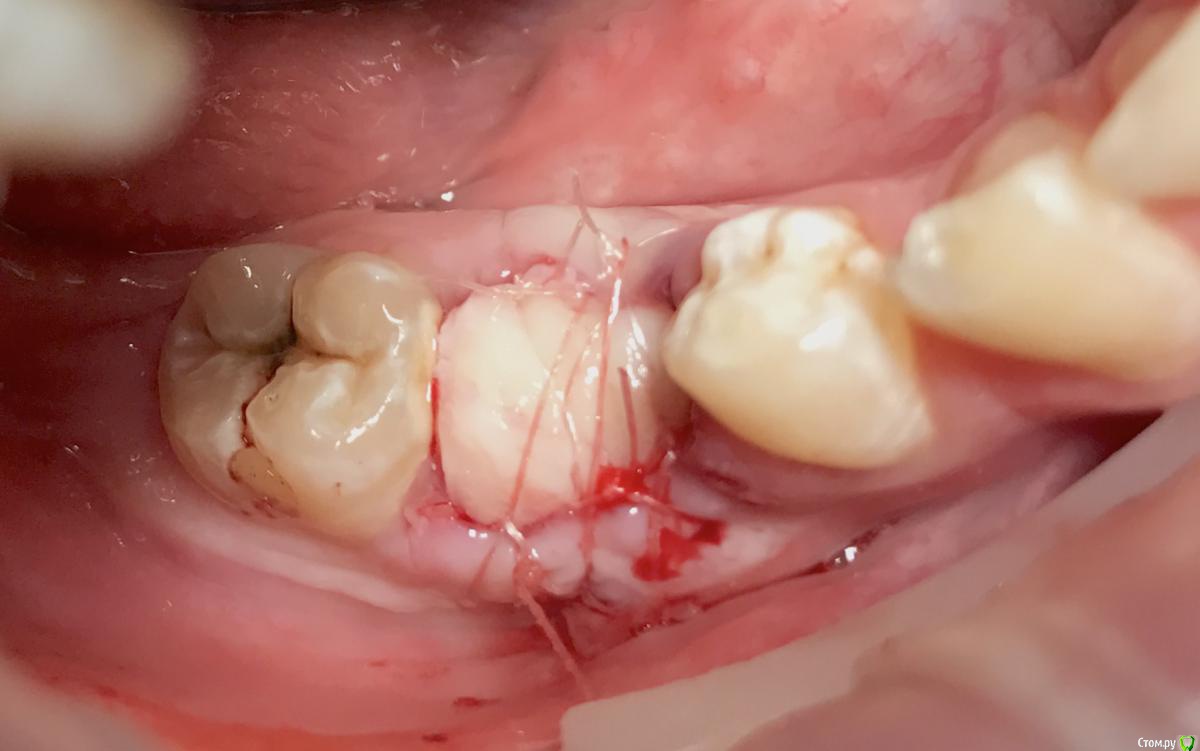

колесников Опубликовано 8 мая, 2017 Поделиться Опубликовано 8 мая, 2017 Немного модифицировал методику Палачи (образование прикреплённой кератинизированой десны междуимплантами,путём выделения и ротирования лоскута с неба). На в/ч у нас обширное поле деятельности со значительными полями кератинизированой слизистой на небе и бугре,что позволяет выделять полосочки не только для пластики в области имплантов,но и для консервации лунки. Можно выделить бугор на питательной ножке и перекинуть его на место 7го. Вариант отсутствует 6ой,присутствует 7ой - выделяем бугор и ведём по маргинальному краю неба у 7го расщепленным разрезом. Длинна может быть значительная,главное свободный конец зафиксировать не в стык а под расщеплённый лоскут принимающего ложа. Одним словом на в/ч с выделением просто. Как быть на н/ч? Обычно только свободный трансплантат с того же неба. Единственный вариант когда можно обойтись местными тканями:отсутствуют нижние 7,8,необходима консервация либо дополнительный объём кератинизированой десны у 7ки. Выделяется с дистального края лунки расщепленная кератинизрованая полоска и далее ведётся по язычному краю лунки . Получаем такую узкую ,но довольно длинную змейку,которую можем зафиксировать медиально, расположив по вестибулярному краю лунки ,либо по язычному ,либо завернуть спиралью. Можно ретромолярно выделить деэпителизированый трансплантат и на подобной змейке перенести его вестибулярно к 7ке. Фото неважные,изначально я не придал значения тому что делаю,позднее результат порадовал объёмом и скоростью регенерации. 1 Ссылка на комментарий

колесников Опубликовано 9 мая, 2017 Автор Поделиться Опубликовано 9 мая, 2017 Да,"приберечь " это про низ. Бугор берётся расщеплённый,не полностью, хорошо регенерирует . Через 4 недели можно брать снова. Травма у нас местно есть в любом случае,кератинизированая расщеплённая десна регенерирует очень хорошо и малоболезненно. Как пример фото разместил :в первом случае со "змейки " я снял швы через неделю и простился,во втором ,где свободный лоскут,остатки его убрал через 3 недели и ещё неделя наблюдений.На фото расщеплённый бугор. На последнем -с выделенным сст. Ссылка на комментарий